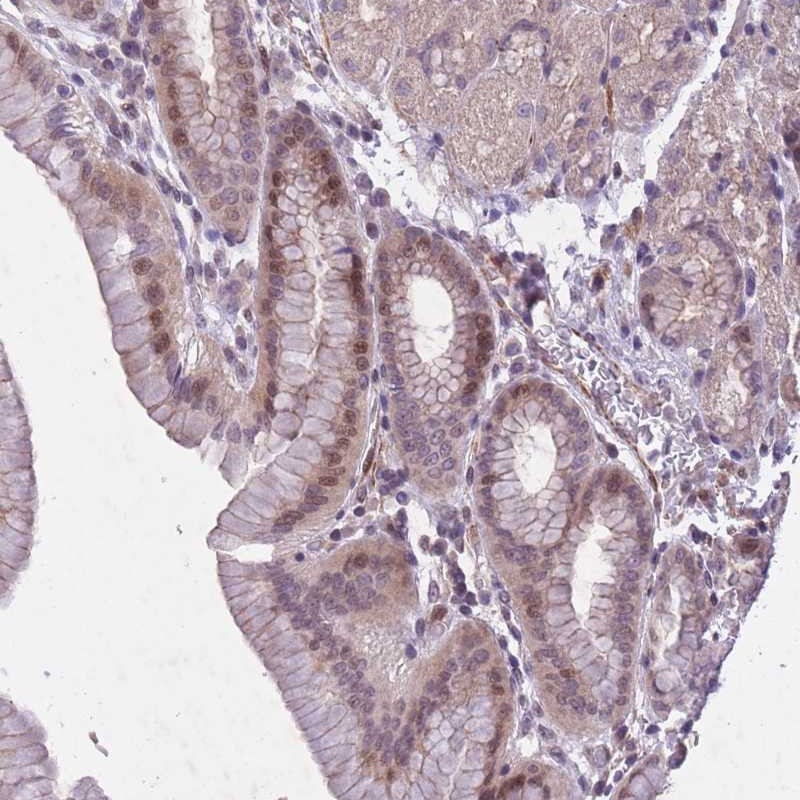

Immunohistochemical staining of human stomach, lower shows moderate nuclear positivity in glandular cells.